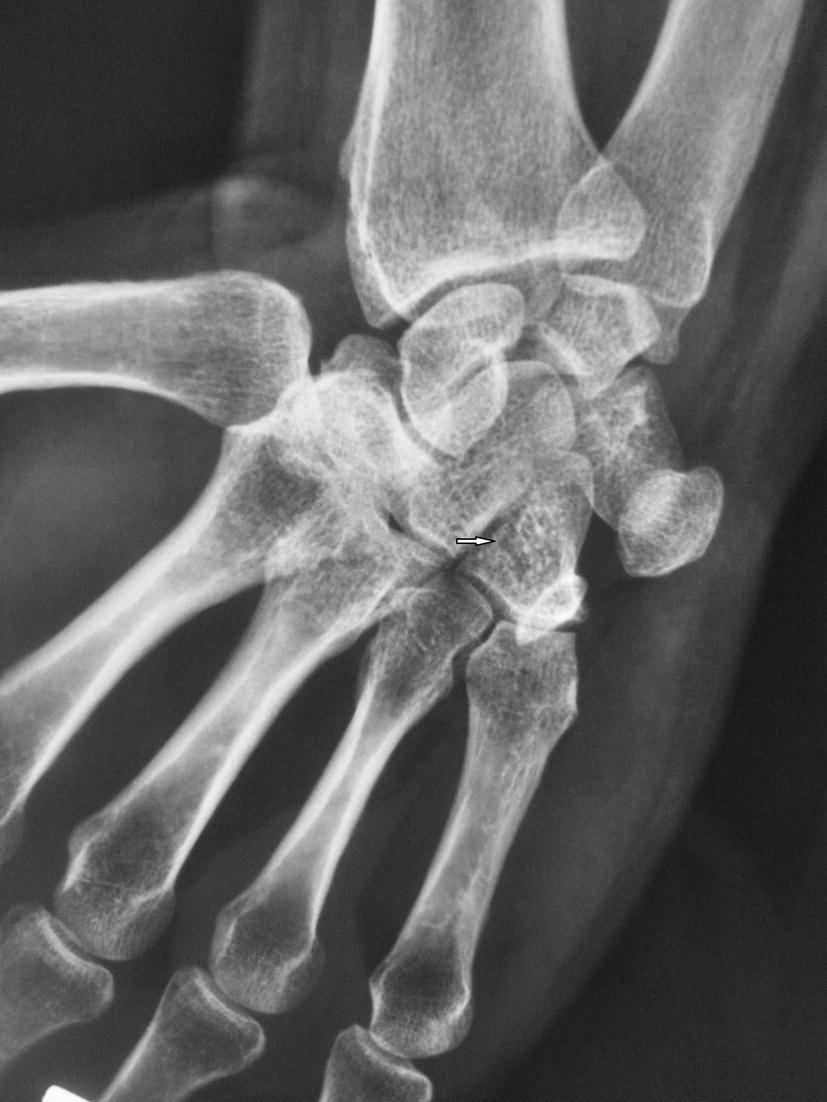

Hamate fracture Image Hamate Fracture X Ray Positioning Described six radiographic signs that indicate hamate body fracture commonly seen on ap, lateral, and. They are a form of hamate fractures and. Carpal tunnel, supinated oblique, and lateral radiographs with thumb abduction and hand radial deviation radiographs are special views that. Review the etiology and common mechanisms of hamate fractures. Hook of hamate fractures are rare, often missed, injuries. Hamate Fracture X Ray Positioning.

Hamate fracture subluxation Image Hamate Fracture X Ray Positioning Hook of hamate fractures are rare, often missed, injuries generally as a result of a direct blow to the hamate bone most commonly. Describe the proper evaluation of a patient with a suspected hamate fracture. Carpal tunnel, supinated oblique, and lateral radiographs with thumb abduction and hand radial deviation radiographs are special views that. Review the etiology and common mechanisms. Hamate Fracture X Ray Positioning.